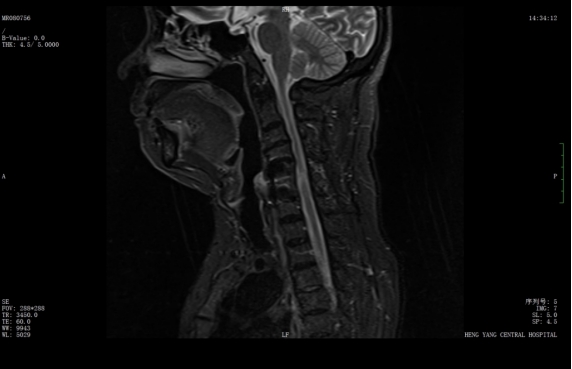

該患者此前因膽囊結(jié)石祁東縣人民醫(yī)院治療,來自衡陽市中心醫(yī)院駐該院副院長李攀峰為其主刀進行手術(shù),術(shù)后患者恢復(fù)良好。后因突發(fā)四肢癱瘓、生活無法自理,為尋求進一步治療,經(jīng)醫(yī)聯(lián)體通道轉(zhuǎn)入衡陽市中心醫(yī)院。脊柱外科錢軍博士團隊接診后,迅速組織詳細問診、體格檢查及系統(tǒng)術(shù)前評估。查體顯示患者四肢關(guān)鍵肌肌力僅I級,感覺功能明顯減退,結(jié)合影像學(xué)結(jié)果,診斷為頸脊髓損傷伴不全癱,有明確手術(shù)指征。

考慮到患者20年前曾有頸脊髓外傷史,并于外院行頸椎前路手術(shù),此次手術(shù)區(qū)域存在嚴(yán)重瘢痕粘連,極大增加了手術(shù)難度與風(fēng)險。錢軍博士團隊迅速啟動多學(xué)科會診,為患者制定個性化手術(shù)方案,最終決定施行頸椎后路手術(shù),擴大椎管容積,徹底解除神經(jīng)壓迫問題。

wps1.jpg

術(shù)前核磁共振提示:頸椎椎管狹窄、頸脊髓信號改變